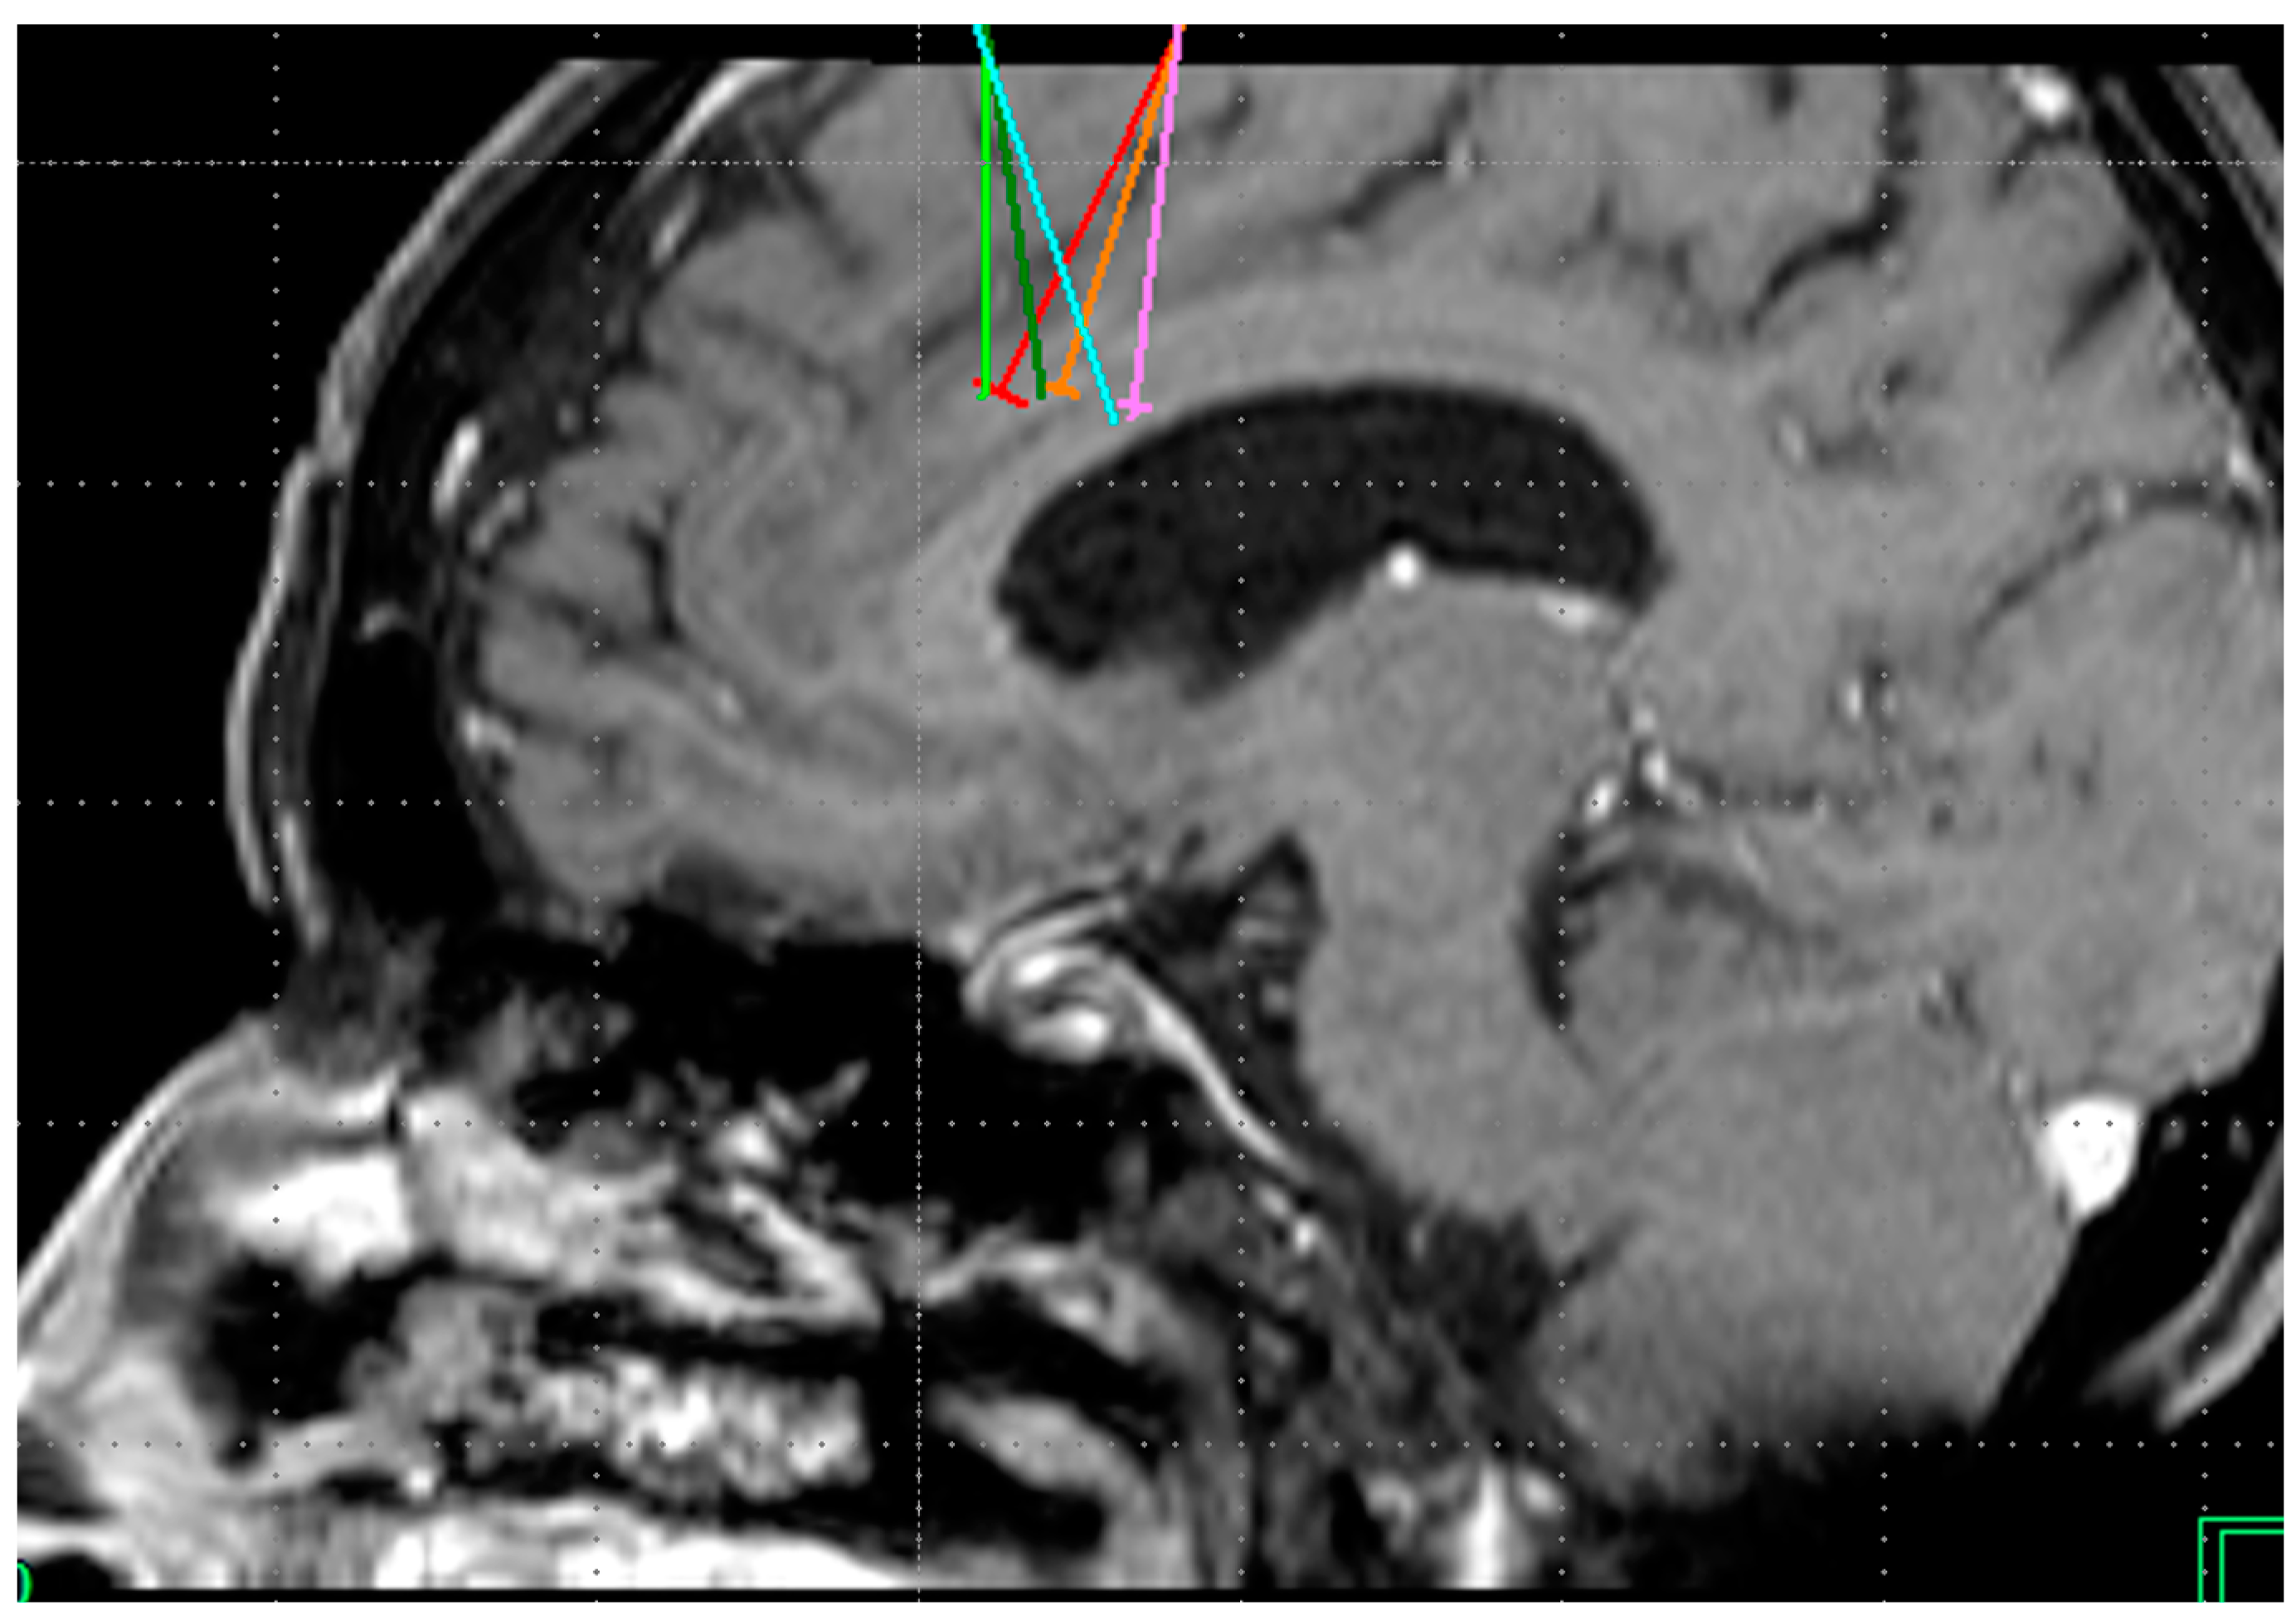

Figure 3.

Bilateral projection of cross-sectional cingulotomy from patient 2. Note hypodense region due to cavernoma.